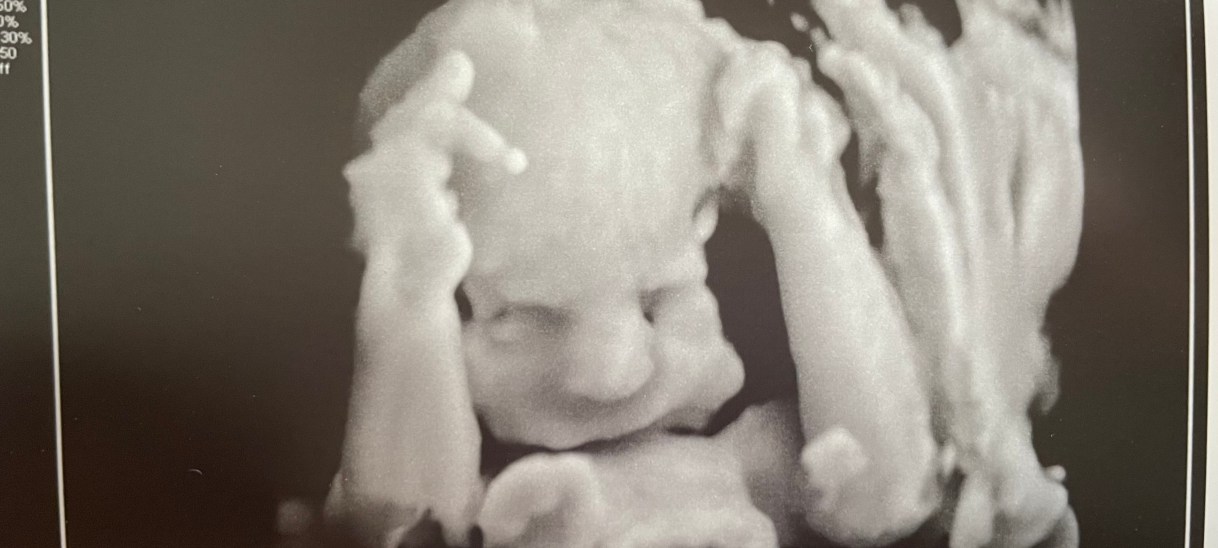

From what they could see at 22 weeks on the anatomy scan, things still looked OK. They just weren’t able to get a good read on her heart nor could they see her profile very well. They were suspicious of her chin, saying that it looked a little small but due to her positioning, they simply couldn’t see well enough to say for sure. We would need to come back.

The next scan was scheduled for a fetal heart echo and to hopefully check her little chin. The echo thankfully went very well, which was a major relief! The typical heart issues associated with Turner Syndrome were not present, but they still couldn’t see her chin. We also learned that I was starting to carry excess fluid and that she had dropped from the 45th percentile to 18th percentile for growth within the month between scans. This coupled with my excess amniotic fluid raised some concerns and we were to come back in 3 weeks.